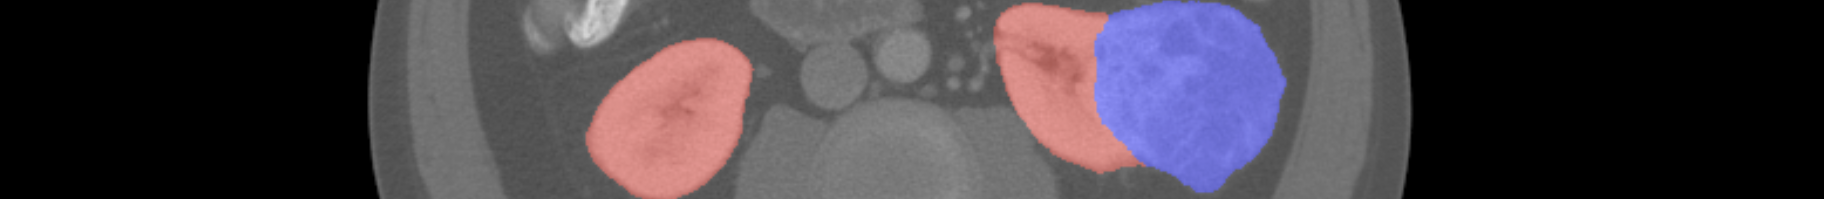

KiTS19

Mean Kidney Tumor Dice

Kidney Dice

Tumor Dice